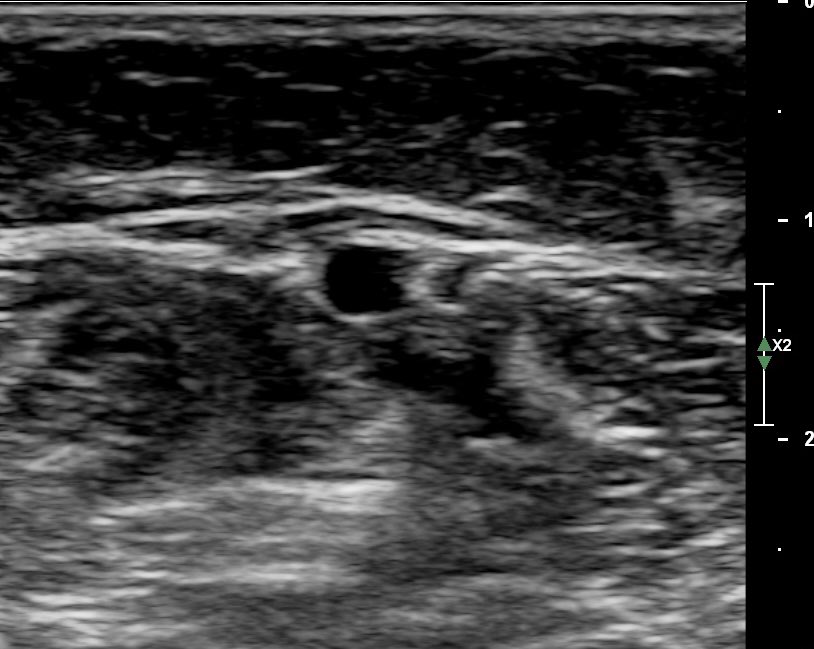

Thromboinflammatory pathways of 🐍 envenoming (bothrops):

•Acute occlusive DVT in veins of the solear plexus: transverse (⚪️) and longitudinal (↖️).

•doi.org/10.3390/ijms24…

#vascularultrasound